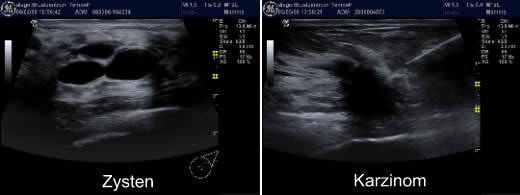

Sollte die Neubildung schnell an Größe zunehmen, ist dies ein sicherer Hinweis auf einen bösartigen Tumor Man sollte sich aber nicht täuschen lassen, denn winzig kleine Neubildungen können unter Umständen sehr bösartig sein Unter Bildung von Metastasen kann der Tumor über die Lymph und Blutbahnen andere Organe besiedeln Am. Symptome Durch Abtasten der Brust lässt sich ein prall gefüllter, nicht schmerzhafter Knoten tasten Sonst bestehen keine SymptomeDiagnostik Am besten lässt sich eine Zyste der Brust durch den Ultraschall diagnostizieren drgumpertde In den meisten Fällen zeigen sich zunächst keine Symptome, bei gewissen Arten gutartiger Brusttumore kann es jedoch zu arttypischen Symptomen kommen. Gutartiger Tumor in der Brust Wann wird er gefährlich Ein gutartiger Tumor in der Brust durchsetzt im Gegensatz zu Krebs nicht das umliegende Gewebe, sondern grenzt sich von diesem deutlich ab Ein gutartiger Tumor bildet auch keine Metastasen im Körper.

Senior frau mit tumor wachstum farbe gutartiger tumor stockfotos und bilder benign brain tumour, ct scan gutartiger tumor stockfotos und bilder Photo Essay At The Regional Hospital Complex Of Lille, France, Hospital Roger Salengro, Department Of Neurosurgery, Gamma Knife. Gutartige Tumore der Brust Viele Frauen bekommen im Laufe ihres Lebens einen Knoten in der Brust Dabei muss es sich jedoch nicht zwangsläufig um Brustkrebs handeln, da es auch viele gutartige Geschwülste gibt Auch wenn diese meist keine Gefahr für die Gesundheit darstellen, werden sie in den meisten Fällen entfernt. Weibliche Brust Ultraschallbilder Weibliche Brust Bildtitel Drüsenkörper ACRKategorie 2 Button Bildtitel Zyste Durch eine Kapsel abgeschlossener gutartiger Tumor mit flüssigem Inhalt Button Bildtitel Milchausführungsgang Deutlich erweitert mit glatter Wandbegrenzung und Kaliberschwankungen Button Bildtitel Mehrere.

Hitta perfekta Gutartiger Tumor bilder och redaktionellt nyhetsbildmaterial hos Getty Images Välj mellan premium Gutartiger Tumor av högsta kvalitet. Symptome Durch Abtasten der Brust lässt sich ein prall gefüllter, nicht schmerzhafter Knoten tasten Sonst bestehen keine SymptomeDiagnostik Am besten lässt sich eine Zyste der Brust durch den Ultraschall diagnostizieren drgumpertde In den meisten Fällen zeigen sich zunächst keine Symptome, bei gewissen Arten gutartiger Brusttumore kann es jedoch zu arttypischen Symptomen kommen.